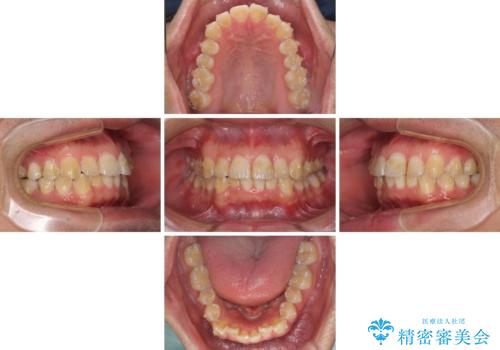

ディープバイトと叢生を解消 インビザライン矯正

- 前歯のデコボコを強い咬みしめを気にして来院された患者様です。

インビザラインを用いて、前歯の叢生を解消するとともに、ディープバイトを改善していくこととしました。

ディープバイトが改善されたことで、顎への負担が軽減され、更には上顎前歯の突出感も改善することができました。

矯正治療後には欠けてしまった修復物をセラミックインレーにて修復治療しました。